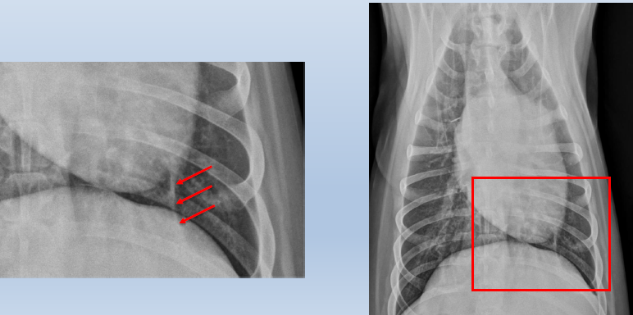

Lateral

2 to 5 left ventricle

5 to 9

Right ventricle

9 to 11

Pulmonary artery

Aortic arch

Right auricle